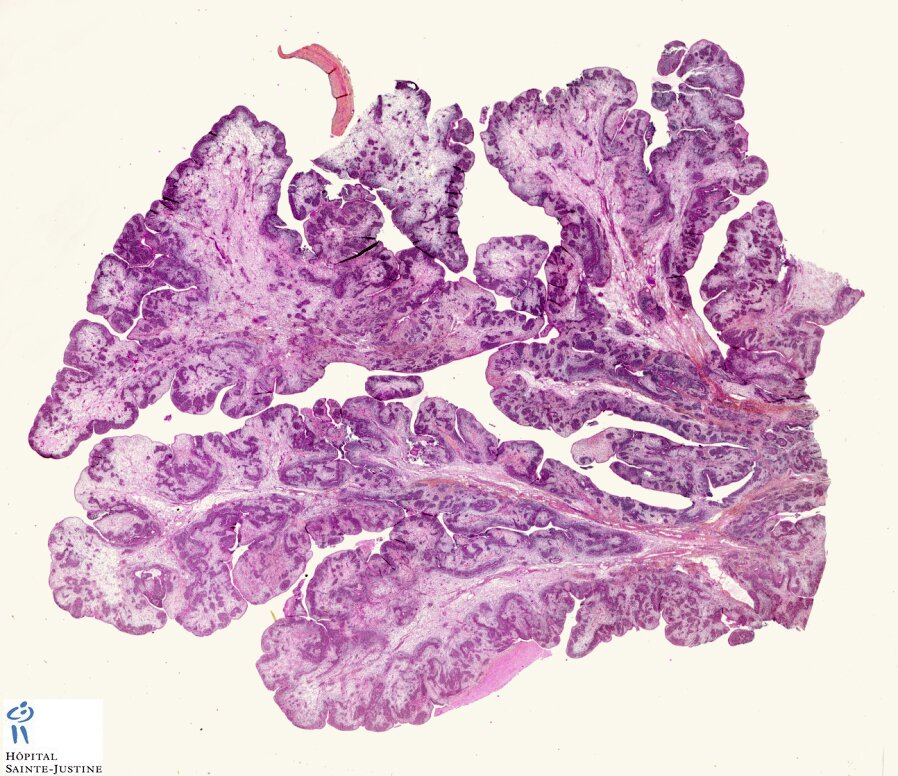

botryoid Wilms tumor

Wilms tumor

(nephroblastoma)